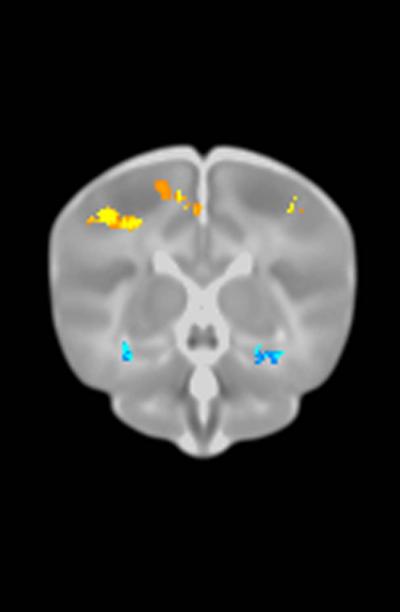

CHAPEL HILL, N.C. – Some brain changes that are found in adults with common gene variants linked to disorders such as Alzheimer's disease, schizophrenia, and autism can also be seen in the brain scans of newborns.

The study included 272 infants who received MRI scans at UNC Hospitals shortly after birth. The DNA of each was tested for 10 common variations in 7 genes that have been linked to brain structure in adults. These genes have also been implicated in conditions such as schizophrenia, bipolar disorder, autism, Alzheimer's disease, anxiety disorders and depression.

For some polymorphisms – such as a variation in the APOE gene which is associated with Alzheimer's disease – the brain changes in infants looked very similar to brain changes found in adults with the same variants, Knickmeyer said. "This could stimulate an exciting new line of research focused on preventing onset of illness through very early intervention in at-risk individuals."